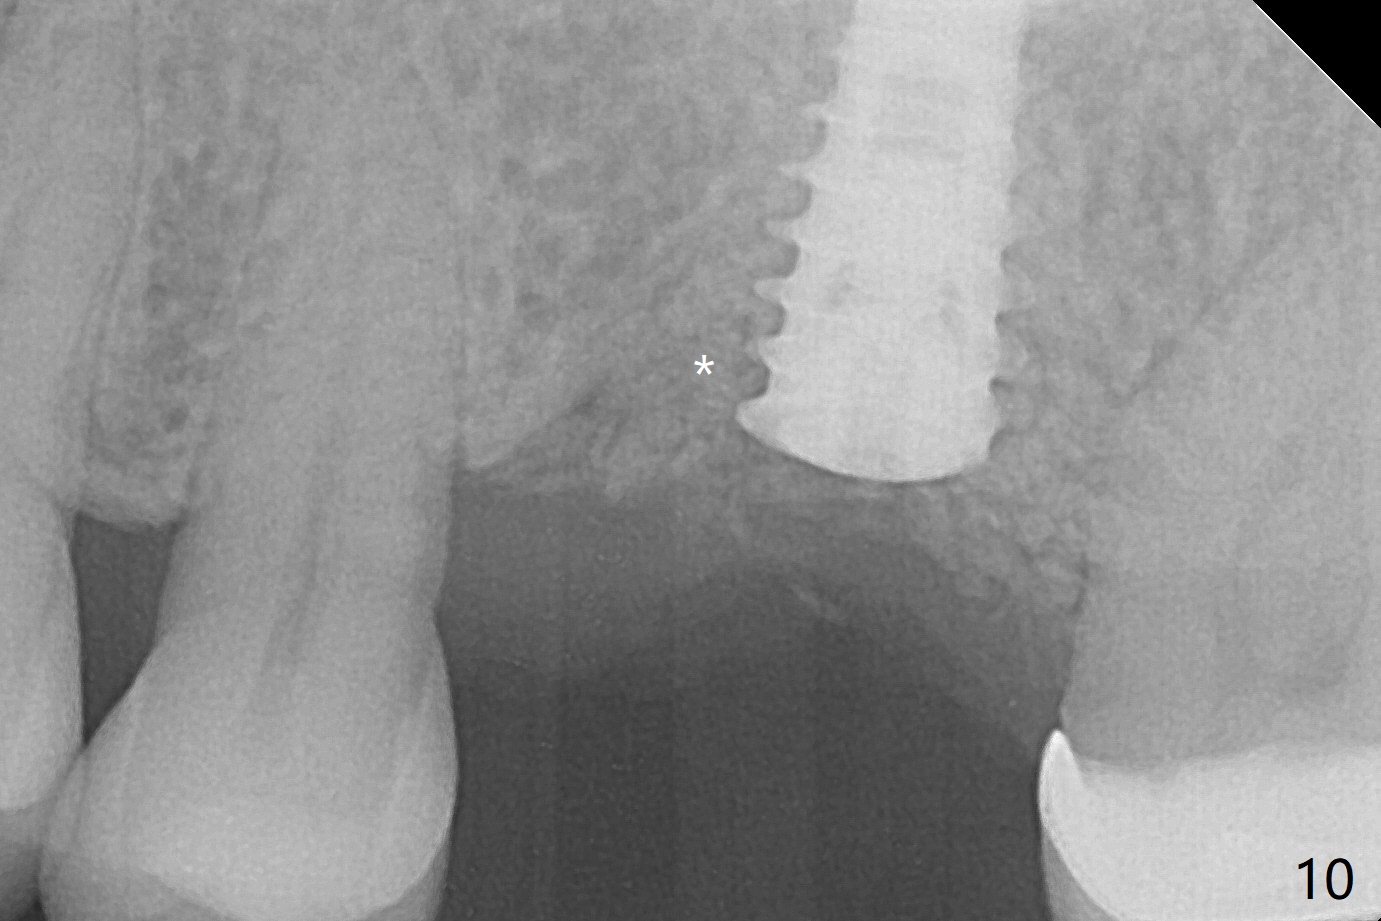

A 57-year-old woman complains of bad smell while use of water flosser between 11 and 21 months post cementation of implant crown at #14 (Fig.1,2). Bone loss is more obvious with CBCT (Fig.3,4), in spite of apparently normal gingiva around the implant after removal of the abutment and crown (Fig.5). In fact the buccal (B) gingiva is fragile with easy access to the underlying implant plateau. Following flap elevation, the bone loss is evident (Fig.6), but the implant plateau is slightly subcrestal (Fig.7 *). The exposed implant threads are covered with the 1st round of bone graft (Fig.8). After 2nd round of allograft (Fig.10-12) and collagen membrane, the flaps are approximated (Fig.9). The wound is covered by acrylic dressing. The latter is loose, but stays in place 1 week postop (Fig.13). Due to short neighboring teeth, the acrylic dressing is able to be removed with wiggling; it appears that the wound is healing (Fig.14). The dressing returns for another 2 weeks; some of the graft has been lost (Fig.15). The dressing does not return 7 weeks postop, since the wound is healing (Fig.16).